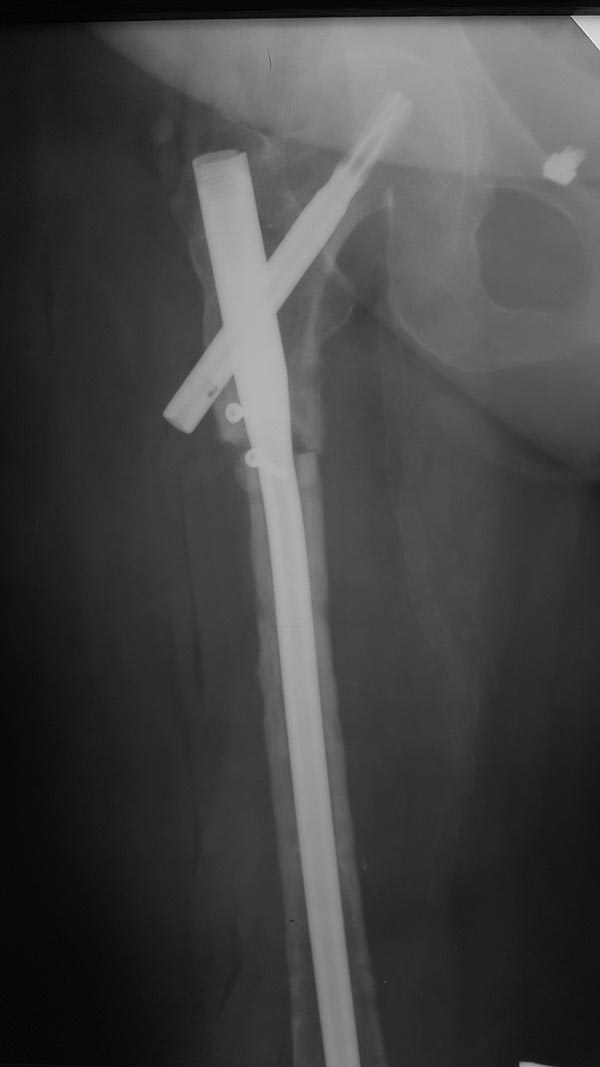

Re: Атрофический псевдоартроз бедра

Операцию сделали, инфекции не выявлено, резецированы концы бедренной кости на 10 - 20 мм с каждой стороны, дистальный конец был нежизнеспособен, щели перелома выполнены губчатым аутотрансплантантом, также по передней поверхности фиксирован винтами губчато-кортикальный аутотрансплантант.

То есть получилось укорочение. Как намерены решать эту проблему?

Клинически укорочение 3,5 - 4 см. Больная была предупреждена о возможной резекции. Возможна компенсация этого укорочения неоперативными методами.